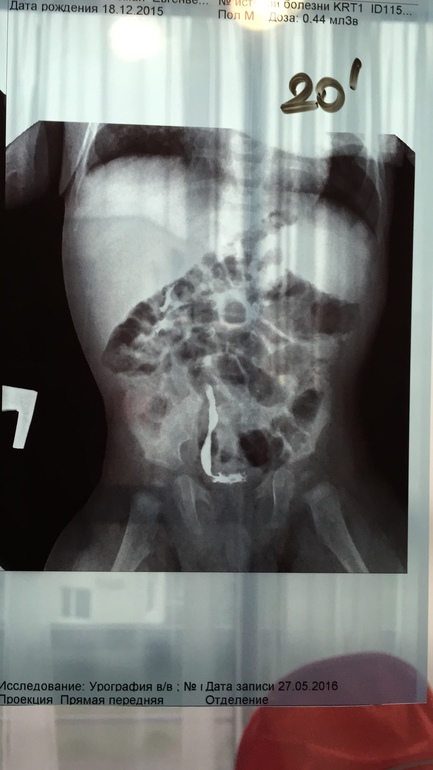

Мультикистоз почки

Да, почка "немая" там нет функции

Вероятно облитерация сосудов не полная и они поддерживают почку